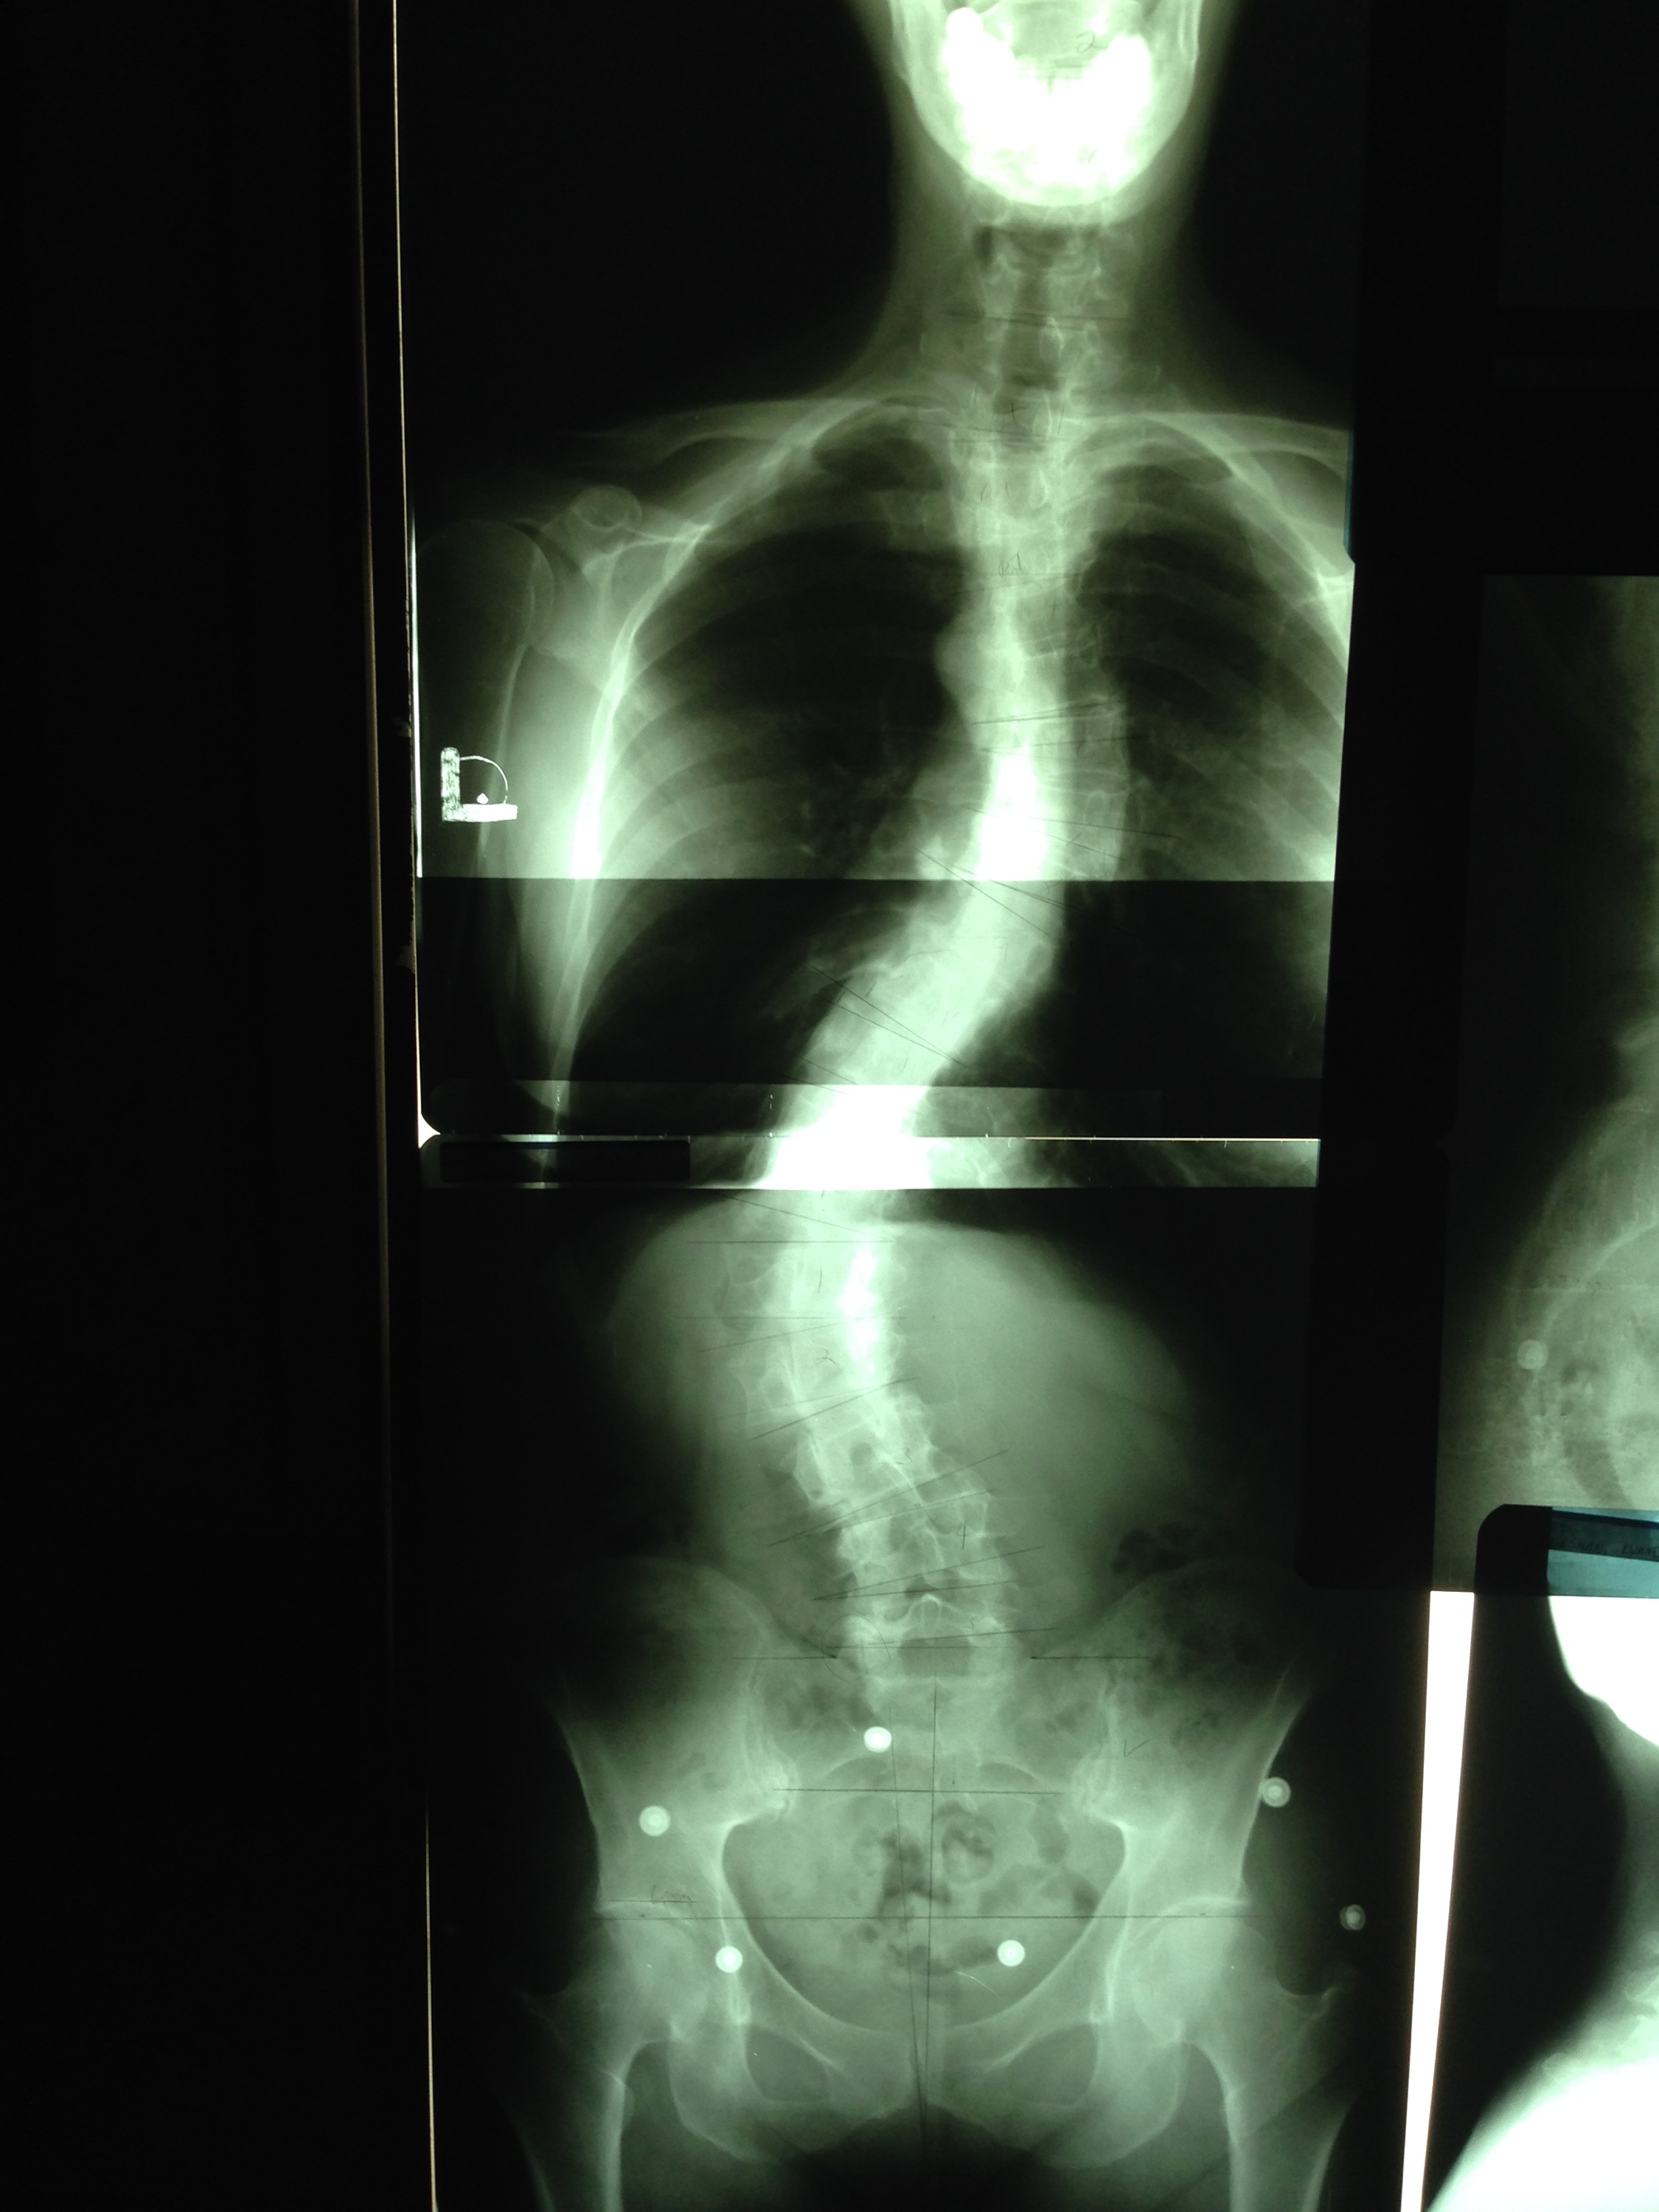

Take a look at the spinal and pelvic radiographs of my friend and colleague, Lynne Ellen Kershaw.

She is 61 years old, with idiopathic scoliosis.

She gave me permission to share her films, because we are both tired of practitioners blaming pain on structure.

It’s a fallacy.